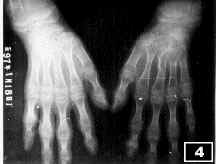

腕关节和近排腕骨发育不良,拥挤移位,表现为舟骨缩小三分之二,月骨呈三角形,三角骨缩小,桡骨远端关节面内倾角11°(正常为27°5′),尺腕角20°(正常为35°4′)。掌指关节和指间关节粗大,关节面不规则,干骺与骨骺早期愈合,关节间隙变窄(图4)。